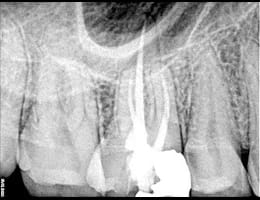

The cleaned canals are filled with a biocompatible material, usually gutta-percha, to seal them and prevent future infection.

gutta core

Superior Filling Materials

GuttaCore: For the best sealing of the root canal system, we use GuttaCore, which provides a 3D fill and superior adaptation to the canal walls.

Lateral Condensation: This technique allows for a dense and well-sealed root canal filling, preventing reinfection and promoting long-term success.